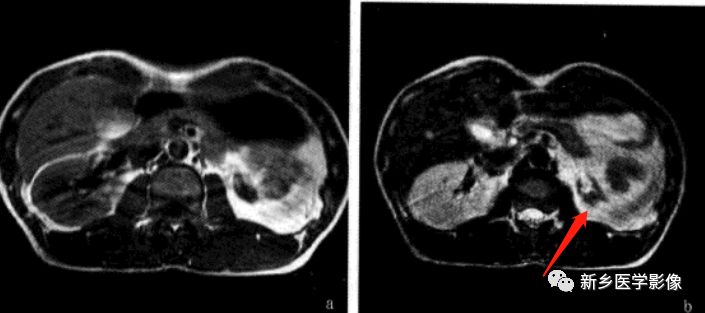

MR特点

常见肾脏形态异常,肾门方向偏前或偏后;肾实质未见异常信号灶,但可见肥大的肾柱等;合并肾积水可见扩大的肾盂肾盏,合并结石可见低信号结石。

讨论

典型的肾脏旋转异常一般通过T1WI和T2WI的横断面和冠状面扫描,发现肾长轴和肾门位置改变而诊断,但合并其他畸形时应注意不要漏诊。